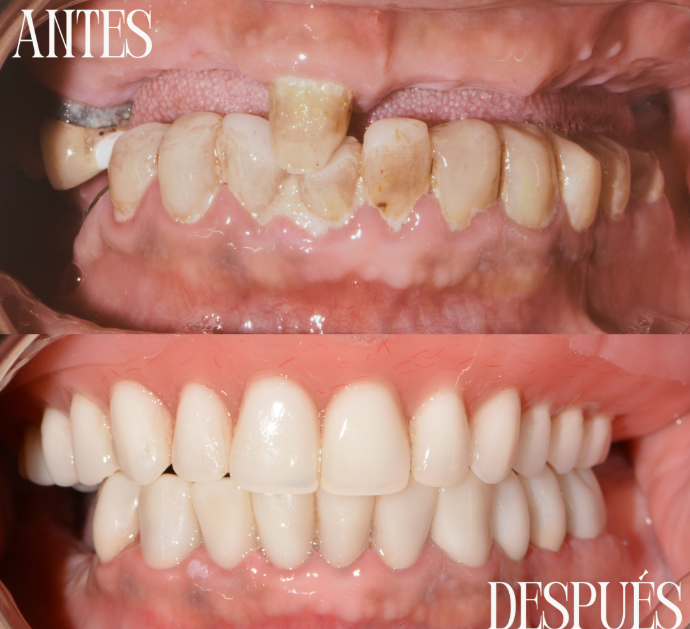

Rehabilitación completa

Rehabilitación integral mediante prótesis removible completa superior de acrílico y restauración inferior con coronas de zirconio. Se recuperan función, estética y estabilidad oclusal, logrando una sonrisa armónica, resistente y de aspecto natural.